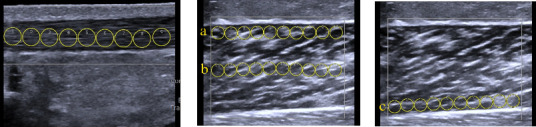

Abstract Image